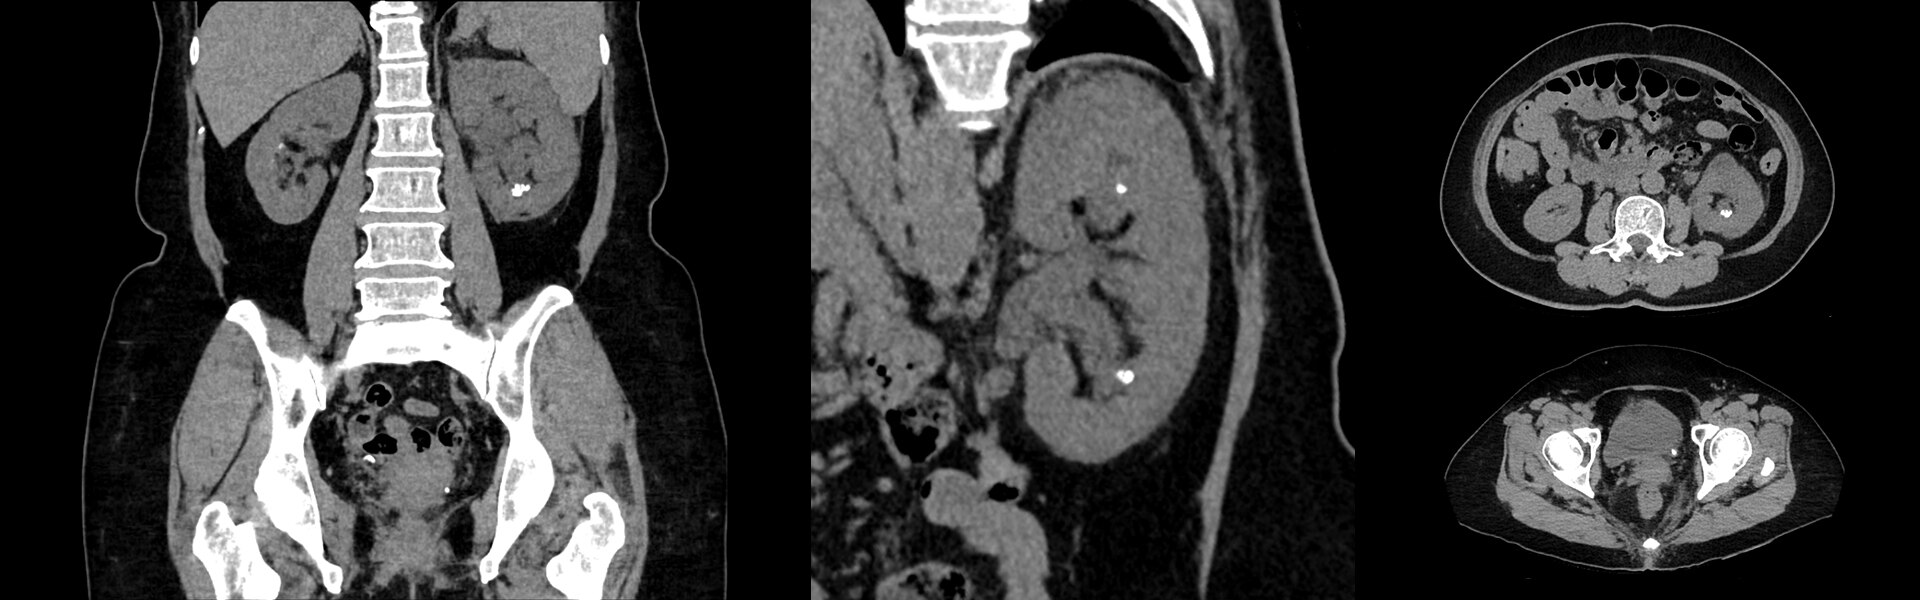

Imágenes clínicas

Varias lesiones pequeñas en las piernas y por el cuello.

La lesión en el oído derecho mide 3,5 mm en el TC. Tumor en la cadera que atraviesa el hueso.

Medición cervical derecha de 6 mm.